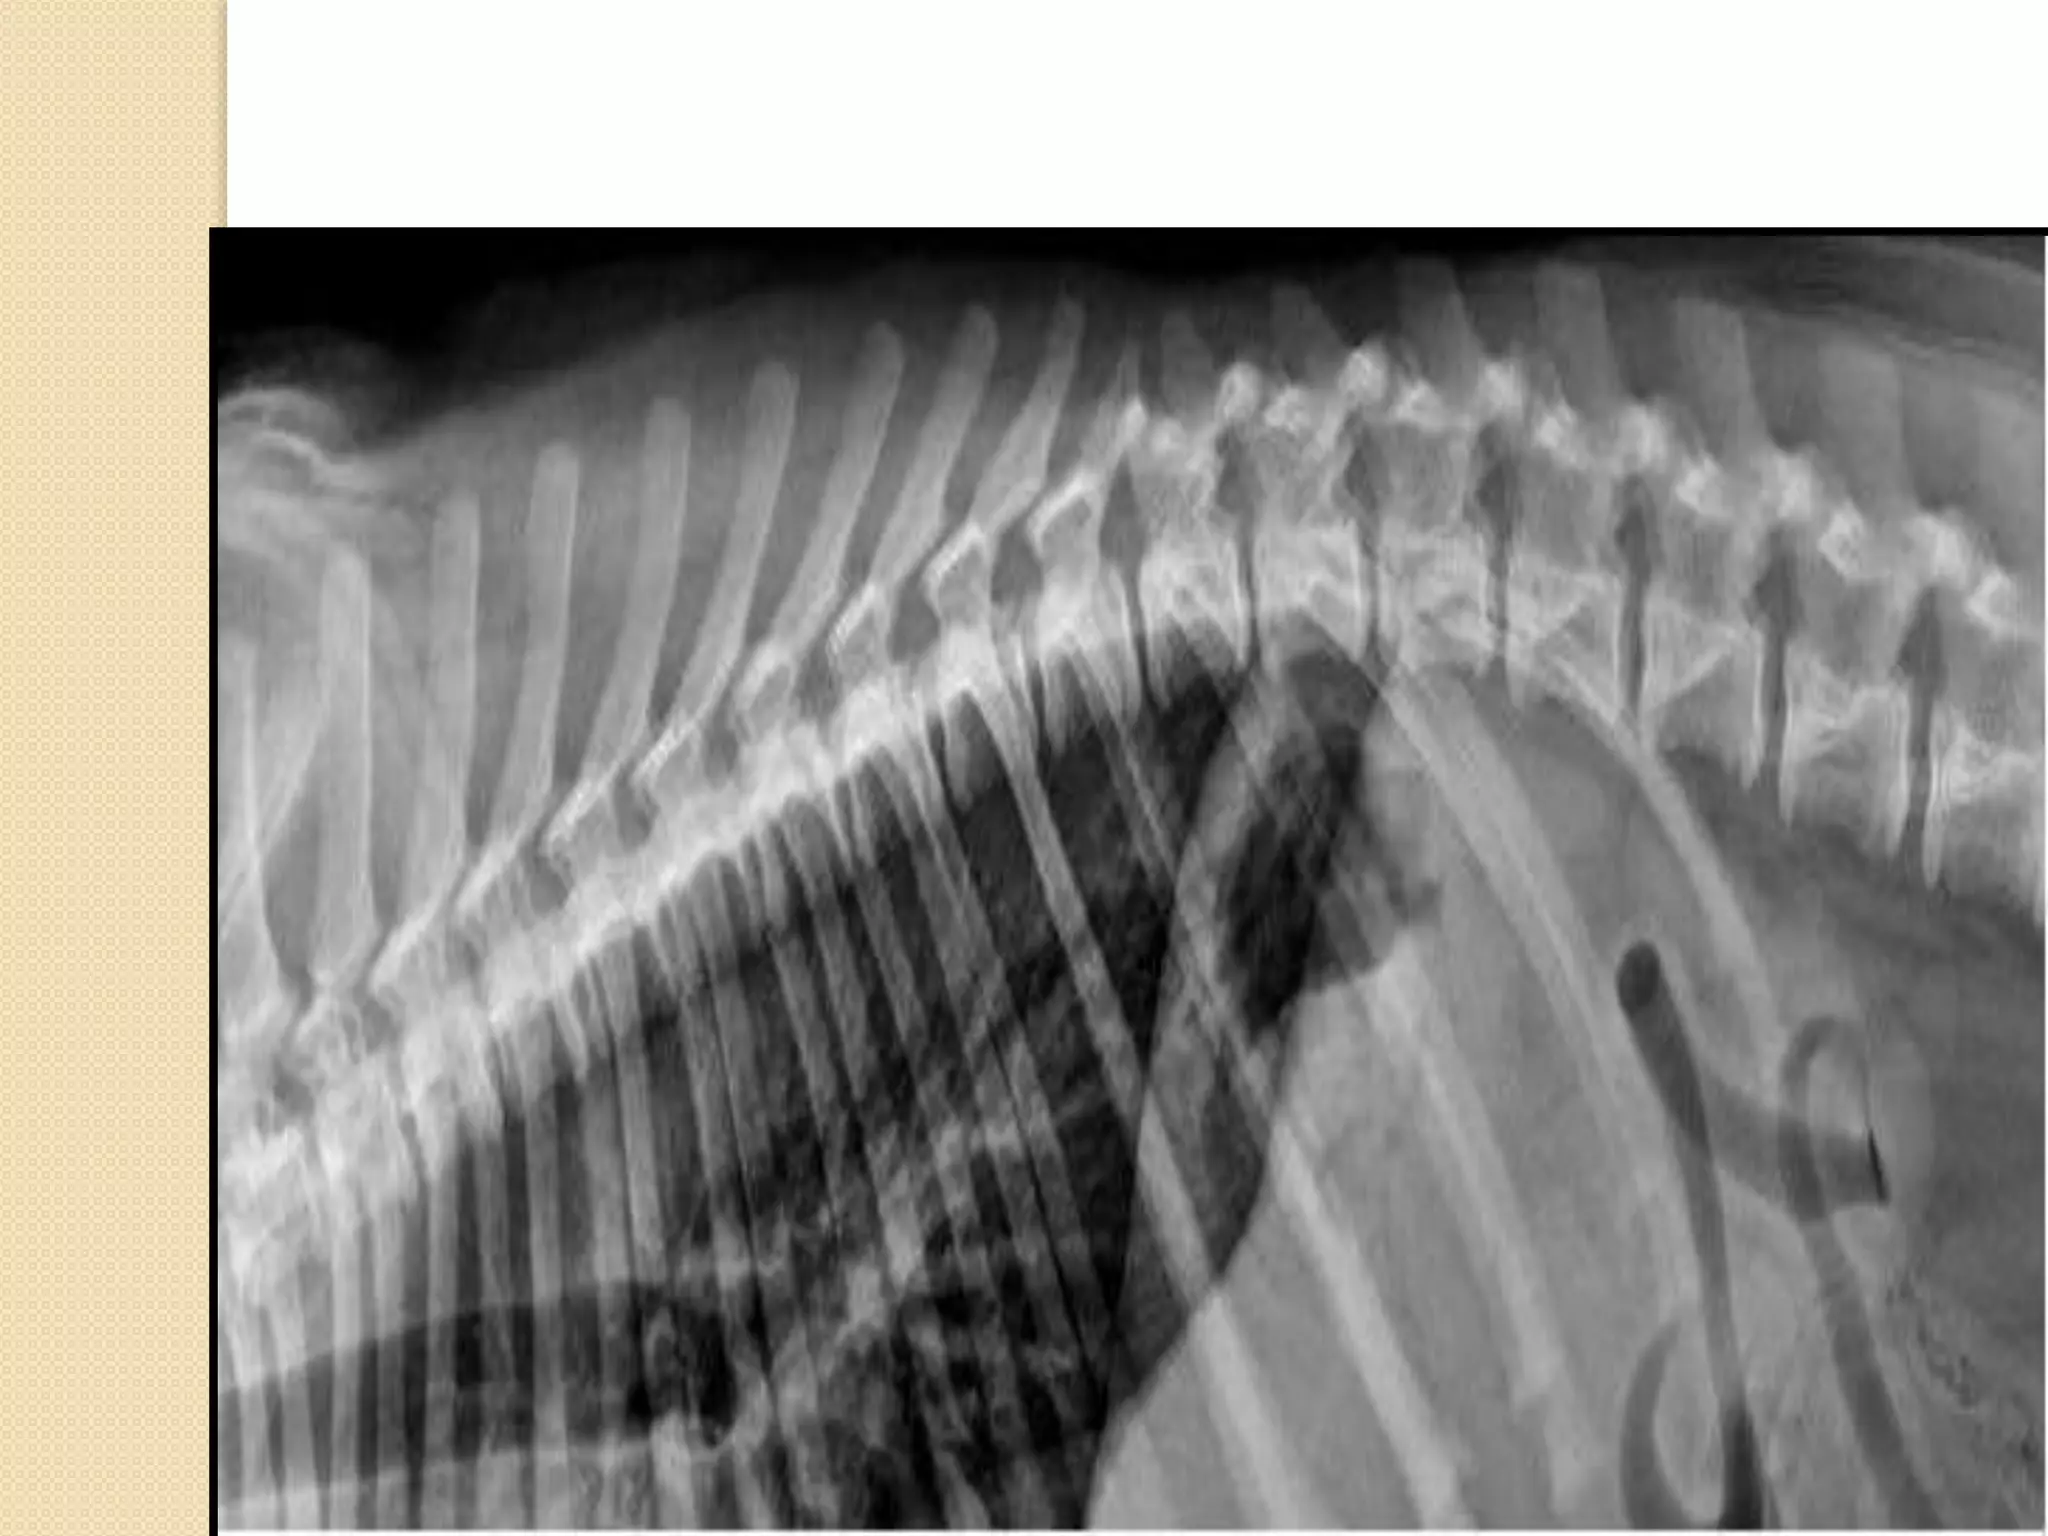

Thoracic vertebrae:

-It is characterised by long spinous process

-The last 3 vertebrae have accessory

processes

-It has articular surface for the rib

articulation

Ribs:

Each rib is a curved rod, which at its dorsal end is movably

articulated to the vertebra, and at its ventral end is either

connected with the sternum, or ends freely. In the dog there are

thirteen pairs of ribs, nine pairs of which are directly connected

with the sternum, while the remaining four end freely and are

known as floating ribs. Each rib is obviously divided into two

parts, a dorsal or vertebral part, and a ventral or sternal

part. The vertebral portion, which forms about two-thirds of

the whole rib, is a flattened, regularly curved rod, completely

ossified. Its dorsal end is rounded, forming the head or

capitulum, which articulates with a concave surface furnished

partly by the corresponding vertebra and partly by the vertebra

next in front. The last three or four however articulate with one

vertebra only

Thoracic cage :

-It is formed :

+Dorsally Thoracic vertebrae

+ventraly Sternum

+Lateraly Ribs

-Thoracic inlet :

+dorsaly 1st thoracic vertebra

+venteraly presternum

+lateraly 1st rib

-Thoracic outlet :

dorsaly  last thoracic vertebra

ventraly  xiphoid process of sternum

lateraly  last rib